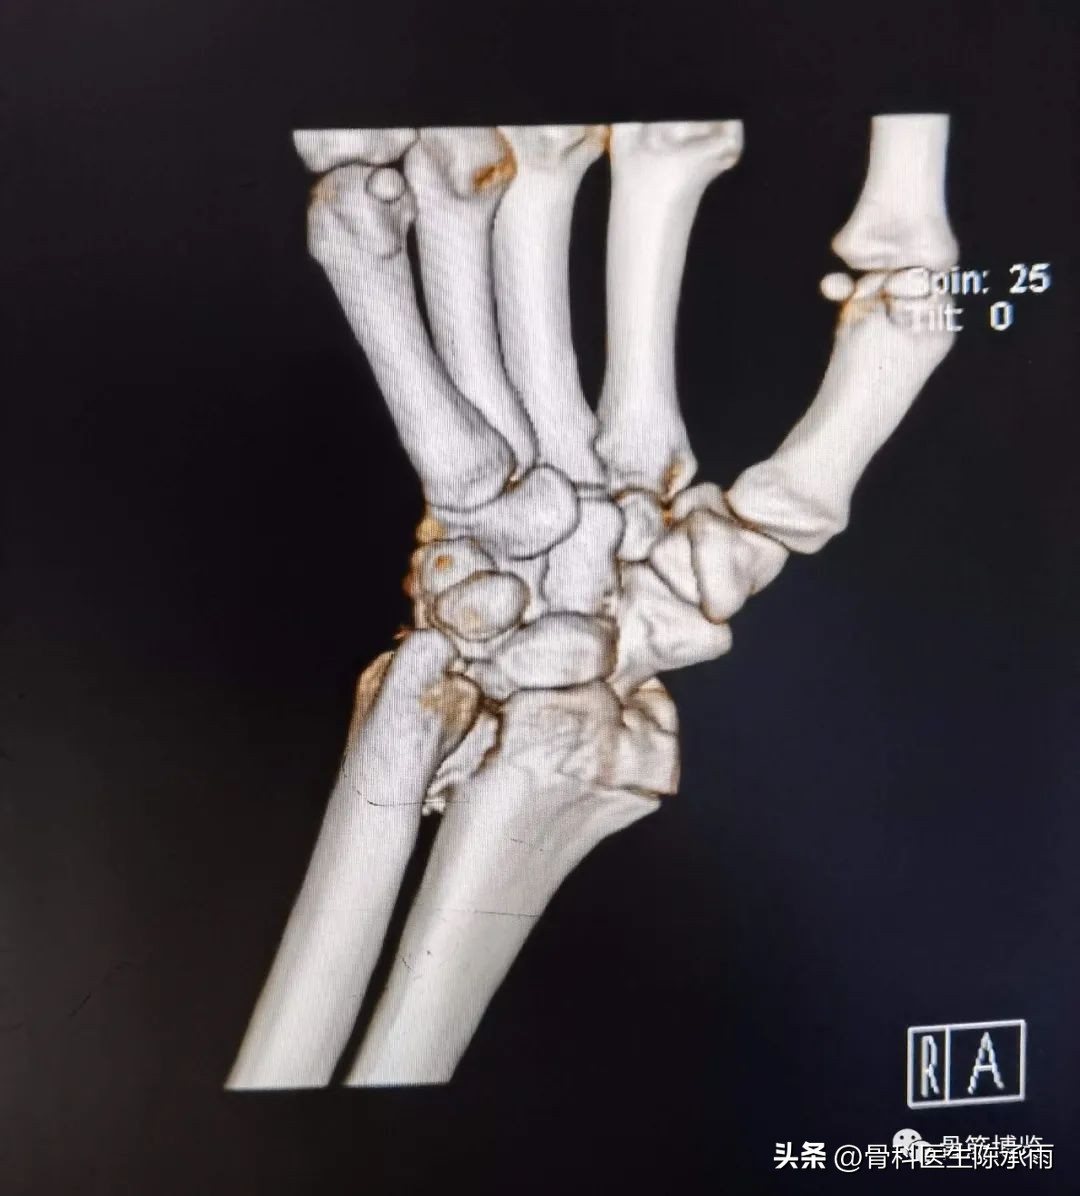

我们这例骨折系关节内陈旧性骨折,且背侧关节面粉碎,并脱位,单纯掌侧或背侧入路手术固定都有较大难度,遂选择掌背侧联合入路手术固定。

术前影像